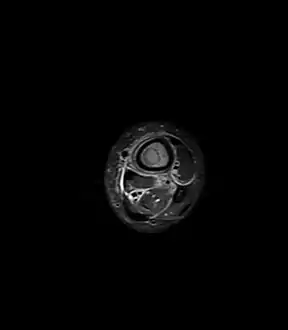

a,b) MRI showing the Brodie's abscess in the left proximal femur

A Brodie abscess is a subacute osteomyelitis, which may persist for years before progressing to a chronic, frank osteomyelitis. Classically, this may present after progression to a draining abscess extending from the tibia out through the skin. Occasionally acute osteomyelitis may be contained to a localized area and walled off by fibrous and granulation tissue.

Oval, elliptical, or serpentine radiolucency usually greater than 1 cm surrounded by a heavily reactive sclerosis, granulation tissue, and a nidus often less than 1 cm. The margins often appear scalloped on radiograph. Brodie's abscess is best visualized using computed tomography (CT) scan. Associated atrophy of soft tissue near the site of infection and shortening of the affected bone. Osteoblastoma may be a classic sign for Brodie's abscess.